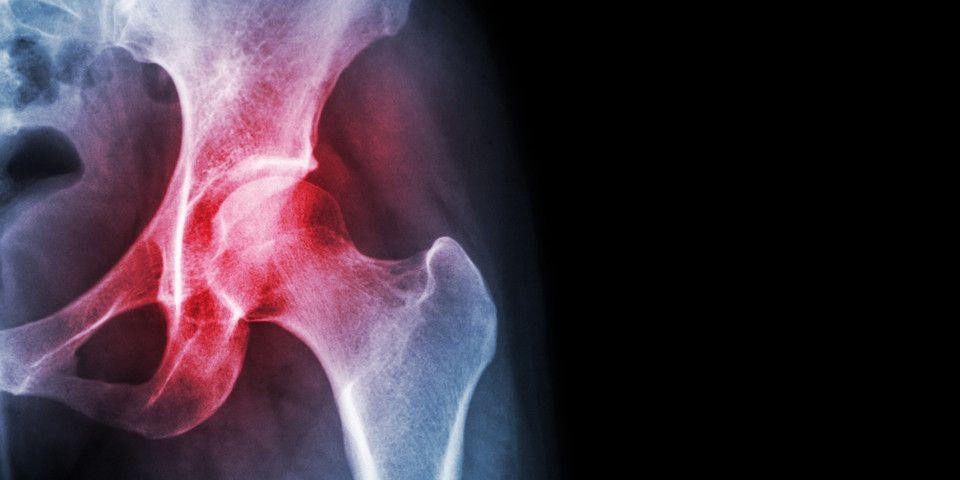

People who experience hip injuries may exhibit symptoms such as pain, discomfort, muscle weakness, and even loss of mobility. Certain hip problems can significantly impede daily activities and quality of life. At Rothman Orthopaedic Institute, we not only understand the intricacies of major non-arthritic hip conditions, such as labral tears and femoroacetabular impingement/FAI (among others); we also routinely treat them. Many Rothman Orthopaedics patients have found relief in hip preservation surgery from our skilled orthopaedic surgeons.

Individuals diagnosed with FAI have an extra bone growth in the bone(s) that form the hip joint. The additional bone growth creates friction when the bones rub together. The three variations of FAI—pincer, cam, and combined impingement—typically lead to pain, stiffness, and limping once the joint becomes damaged.

Many athletes are all too familiar with labral hip tears. When the labrum cartilage between the ball (femoral head) and socket (acetabulum) experiences either abrupt trauma—through a sports-related collision—or through repetitive movement over time, the result can be a labral tear. The primary symptom of a hip labral tear is deep pain resonating in the hip joint.